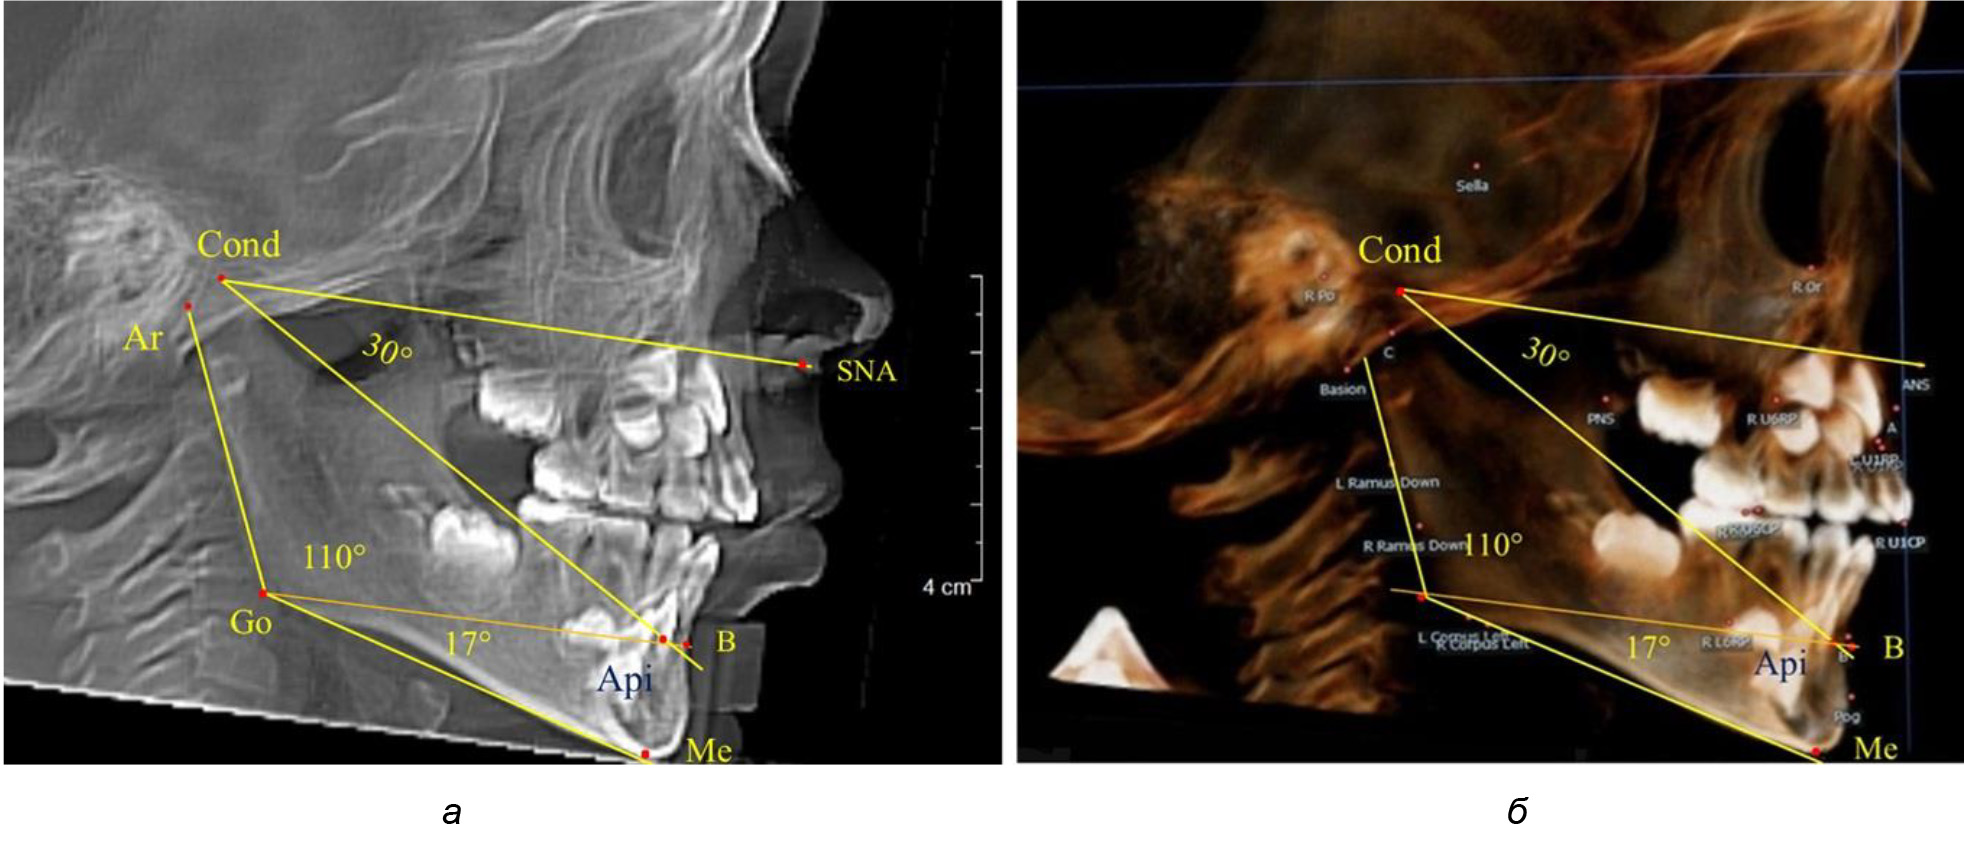

Через апикальную точку нижнего резца от суставной точки проводили линию Cond-Api, которая с линией Cond-SNA образовывала угол гнатический части лица SNA-Cond-Api, используемый для оценки ее основных параметров.

Кроме того, угол нижней челюсти Ar-Go-Me линией Go-Api делили на две составляющие. Верхняя часть угла Ar-Go-Api определяла значение альвеолярного нижнечелюстного угла, а угол Api-Go-Me определял особенности части тела нижней челюсти (рис. 1).

Рис. 1. Расположение реперных точек (а) и линий (б) для оценки угловых параметров гнатической части телерентгенограммы

При анализе ТРГ 5 детей в периоде прикуса молочных зубов отмечено, что величина основного угла гнатической части лица SNA-Cond-Api, как правило, в норме составляла около 30°, и его величина была относительно стабильной у всех обследованных детей. В то же время угол нижней челюсти и его составляющие отличались вариабельностью параметров при различных показателях нижнечелюстного угла (рис. 4).

Рис. 4. Особенности ТРГ (а) и 3D-модели (б) в периоде прикуса молочных зубов

Таким образом, в периоде молочного прикуса с оптимальными окклюзионными соотношениями, несмотря на линейные размеры в вертикальном и сагиттальном направлении, которые, безусловно, меньше параметров взрослых людей, величина основного угла гнатической части лица SNA-Cond-Api соответствовала параметрам людей с полностью сформированным физиологическим прикусом постоянных зубов. Анализируя данные рентгенограмм детей в периоде сменного прикуса, отмечено, что величина основного угла гнатической части лица SNA-Cond-Api, так же как в молочном и постоянном прикусе, в норме составляла от 28 до 32°. В то же время угол нижней челюсти и его составляющие отличались вариабельностью параметров при различных показателях нижнечелюстного угла. Достоверных различий угла гнатической части после смены нижних медиальных резцов и прорезывания первых постоянных моляров (4 ребенка) не было; происходил очередной этап подъема высоты прикуса и увеличение линейных размеров костей гнатической части, однако угловые параметры были относительно стабильны. После смены всех резцов и замены первых молочных моляров первыми премолярами (6 человек) увеличивались линейные размеры при сохранившихся угловых показателях гнатической части лица (рис. 5).